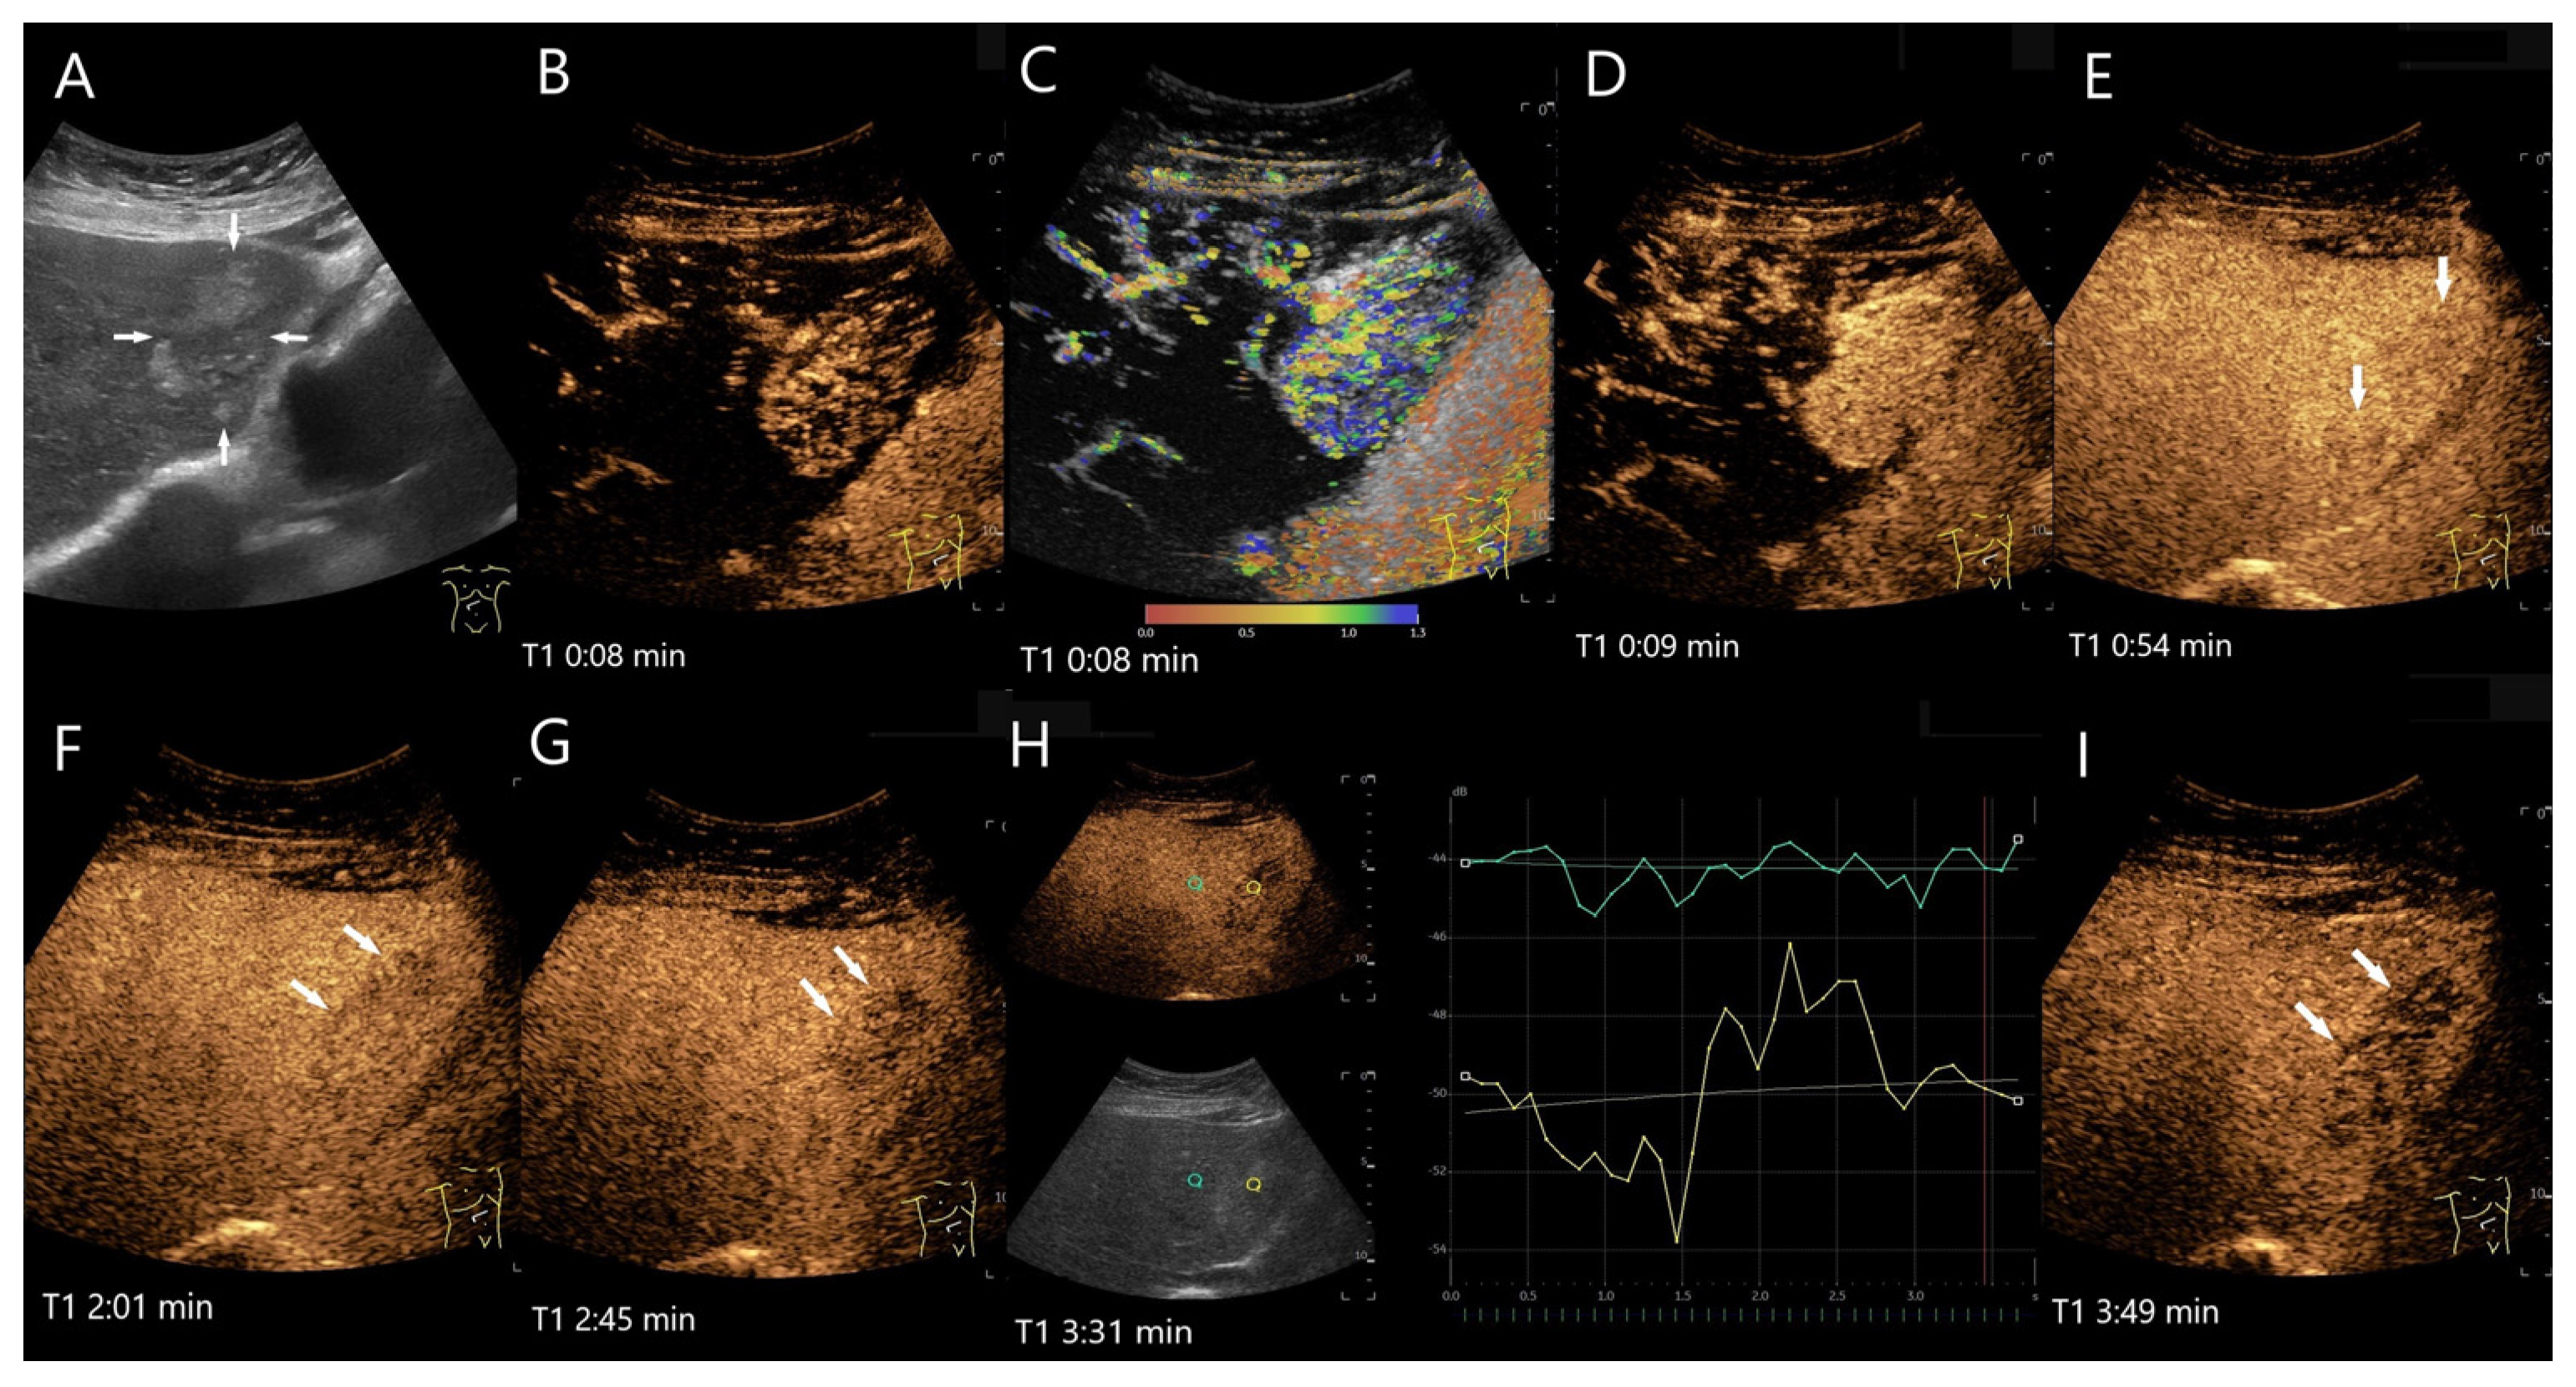

Figure 18.

Hepatic PEComa. In the left lobe of the liver there is a more than 5 cm large, oval, irregularly demarcated heterogeneous lesion (arrows) with several hyperechoic areas (A). In the AP of the CEUS (B) and in parametric imaging (C), the enhancement is initially lateral. The parametric imaging shows the chronological sequence of the arrival of the UCA in color. Then, the lesion is homogeneously hyperenhanced (D). In the PVP before 60 s, the hypoechoic parts show mild hypoenhancement (arrows) (E). The hyperechoic parts are isoenhanced or even slightly hyperenhanced. The hypoenhancement is slightly more pronounced at the beginning of the LP (F). This increases in the course of the LP (G) and is objectified in the time intensity curve (H). In the advanced LP the lesion shows a significant hypoenhancement (I). The washout with hypoenhancement was the reason for the US-guided biopsy, which resulted in a PEComa. This was confirmed by the histology of the surgical specimen.